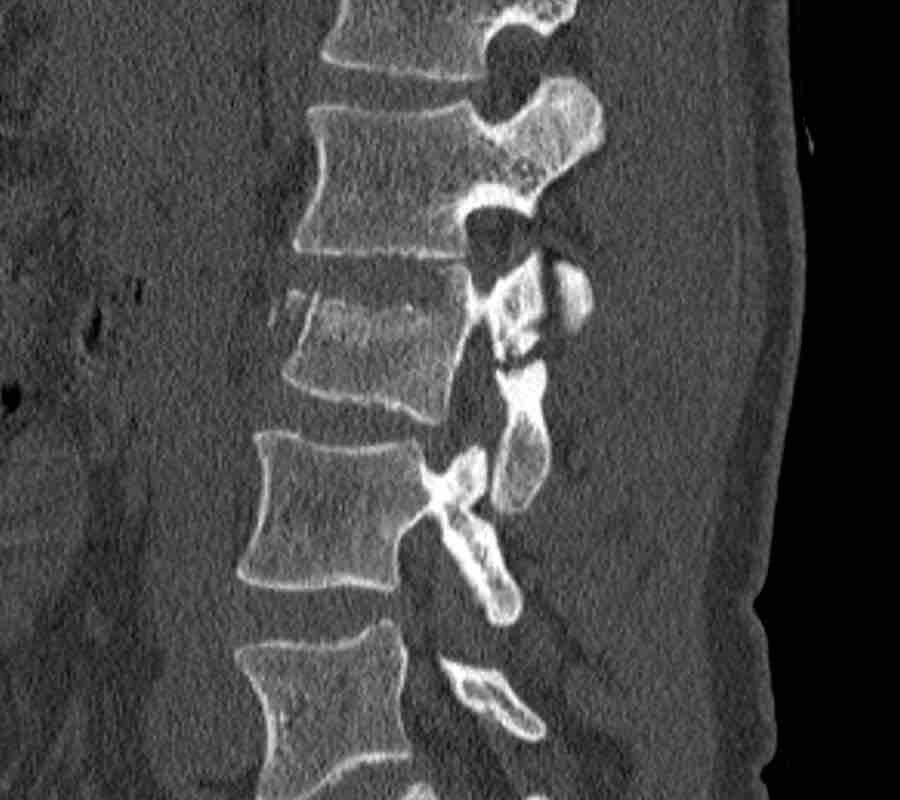

Scroll through the images.

What is the highest AO-type of injury?

Any additional findings?

Findings

- Subtle widening of the interspinous distance (white circle)

- Small avulsion fracture spinous process (yellow arrow)

- Compression fracture with involvement of one endplate and posterior wall (1+2 points)

Conclusion

Injury type B2 + A3